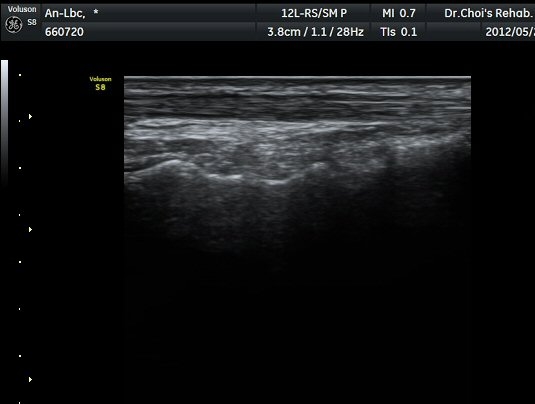

¹ß¸ñ ¾Õ Ⱦ´Ü¸é°Ë»ç¿¡¼­ Àü°æ°Ç(TA), ¾öÁö½ÅÀü°Ç(EPL), ¹ß°¡¶ô½ÅÀü°Ç(EDL)ÀÇ ºÎÁ¾ ¹×

°Ç ÁÖÀ§ ¼ö¾× Àú·ù°¡ °üÂûµÈ´Ù(»çÁø 1, 2). °ÇÀÇ ºñÈÄ¿Í ¼ö¾×Àú·ù´Â °ÇÃø(»çÁø 4)°ú ºñ±³Çϸé

¶Ñ·ÈÇÏ´Ù. Àü°æ°Ç Á¾´Ü¸é°Ë»ç¿¡¼­ °ÇÀÇ ºÎÁ¾°ú °Ç ÁÖÀ§ ¼ö¾× Àú·ù°¡ °üÂûµÈ´Ù(»çÁø 3). °ÇÀÇ

ºÎÁ¾°ú ¼ö¾×Àú·ù´Â °ÇÃø°ú ºñ±³ÇÏ¸é ¶Ñ·ÈÇÏ´Ù(»çÁø 5).¤·